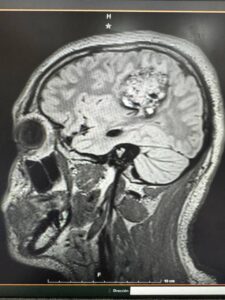

Un hecho sin precedentes ocurrió en Yucatán: especialistas del IMSS lograron realizar la primera craneotomía en un paciente pediátrico consciente. El joven de 16 años permaneció despierto mientras los médicos extirpaban un tumor cerebral de 5 centímetros, permitiendo monitorear en tiempo real su lenguaje, movilidad y funciones cognitivas.

Tras seis horas de intervención, el tumor fue retirado exitosamente al 100% y el paciente preservó sus funciones motrices y del habla, marcando un hito histórico en la medicina de Yucatán y del país.